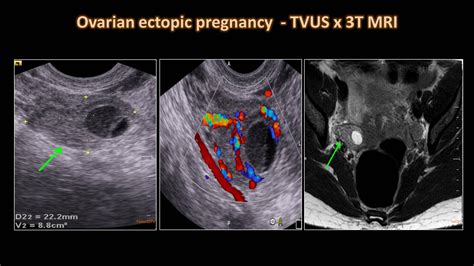

When a physician suspects an ectopic pregnancy, they often perform a transvaginal ultrasound. This procedure uses a specialized wand to provide a high-resolution view of the reproductive organs. By visualizing the uterus, ovaries, and the surrounding areas, radiologists and OB/GYNs look for specific clinical markers.

When doctors look for an ectopic pregnancy by ultrasound, they are essentially looking for an "empty" uterus where there should be a pregnancy sac. The diagnostic process typically involves:

• Locating Adnexal Masses: A mass outside the uterus in the adnexal region (where the fallopian tubes and ovaries are located) often suggests an ectopic implantation.

• Checking for Free Fluid: The presence of free fluid in the pelvic cavity, especially in the pouch of Douglas, can indicate internal bleeding caused by a rupture.